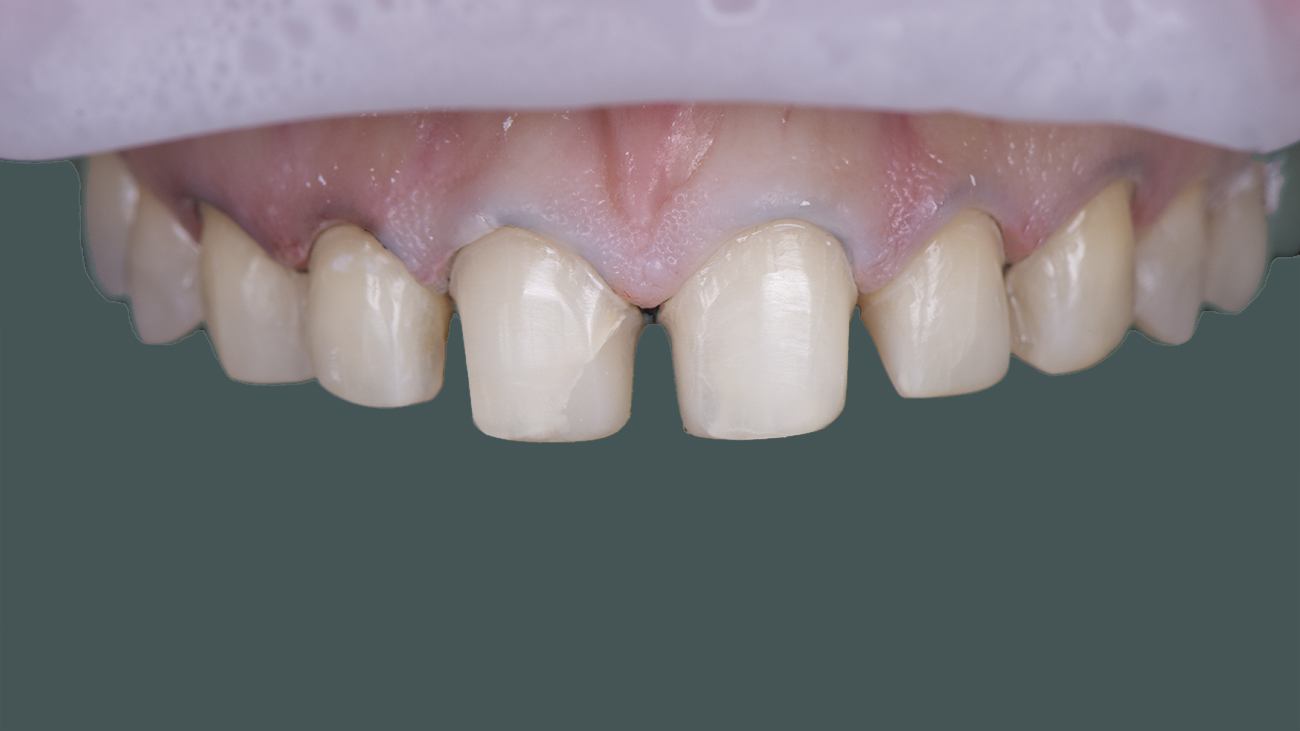

Отбеливание зубов

Наша процедура отбеливания зубов с лампой Beyond представляет собой безопасный и эффективный метод для придания вашей улыбке яркости. С использованием передовой технологии лампа Beyond излучает специализированный свет, активизируя отбеливающий гель на ваших зубах. Этот процесс помогает устранить пятна и изменение цвета, обеспечивая заметные результаты уже после одной сессии. Приготовьтесь к ослепительной улыбке, которая приобретет уверенность, став на несколько оттенков светлее!

Отбеливание зубов представляет собой процедуру, применяемую в стоматологии для удаления пятен и окрашивания зубов, создавая более светлую и привлекательную улыбку. Это включает нанесение отбеливающего агента на поверхность зубов, который может быть активирован с помощью источника света или через контролируемые химические реакции. Процедура отбеливания зубов может быть выполнена в стоматологическом кабинете или дома под наблюдением стоматолога. Важно следовать профессиональным рекомендациям и соблюдать инструкции, чтобы достичь безопасных и эффективных результатов.